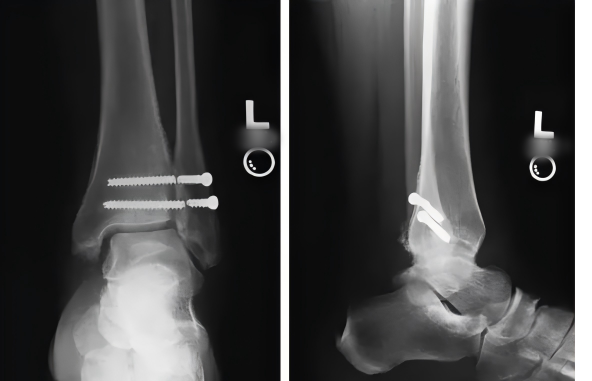

傳統手術金屬螺釘固定(ding)存(cun)在風險(xian):

不符合踝(huai)關節下(xia)脛腓聯(lian)合生(sheng)理(li)微動

完全負(fu)重(zhong)前需(xu)局麻取(qu)出

非取出易產生:螺(luo)釘松動、斷裂(lie),螺(luo)釘周圍骨質(zhi)吸收和溶解

完全負重推(tui)遲導致的(de)股(gu)四頭肌等肌肉萎縮(suo)